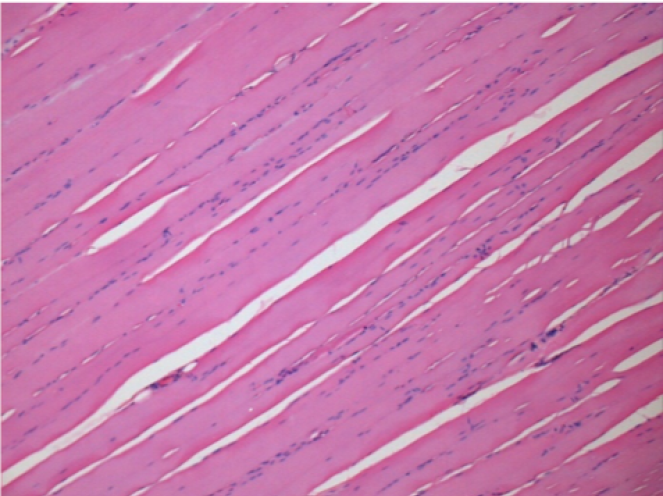

1 mes después de la inyección de Endopeel

1 mes después de la inyección de Endopeel 0,1 ml en el músculo pretibial derecho.

¡Lo que se ve en negro en las imágenes no es una necrosis como podrían imaginar algunos científicos!

De hecho, hay que tener en cuenta 4 conclusiones

- un artefacto de coloración

- una ausencia de necrosis

- una apoptosis

- un proceso biorregenerativo

L : Control-100xD30

R:100xD30

R :400xD30